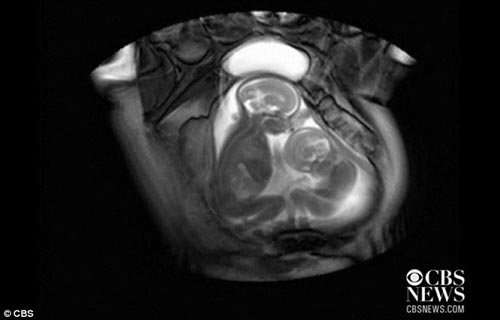

功夫秀:最新磁共振扫描图像显示孕妇体内一对双胞胎儿“拳脚相加”

英国伦敦帝国理工学院使用磁共振成像扫描孕妇腹内双胞胎儿,发现双胞胎儿在母体中争夺“地盘”

英国伦敦帝国理工学院磁共振扫描仪拍摄图像显示了令人惊奇的一幕——母亲子宫中的双胞胎为争夺生存空间而打斗。这对胎儿在母体中已孕育20个星期,在这项研究中并不清楚胎儿性别以及母亲的身份。

玛丽莎-克拉克博士扫描监控24对患有双胞胎输血综合症的双胞胎,她说:“这将使我们能够看到双胞胎儿彼此间的位置,他们在子宫中占据多大的空间,以及他们如何移动,彼此间如何推挤踢踹。”

这种扫描又叫做“静默-磁共振成像”,能够比超声波获得更为详细的图像资料。但是玛丽莎称,该技术不应当经常用于孕妇检查,虽然这种扫描可能帮助我们发现重要信息,但是它将令孕妇非常紧张。(卡麦拉)